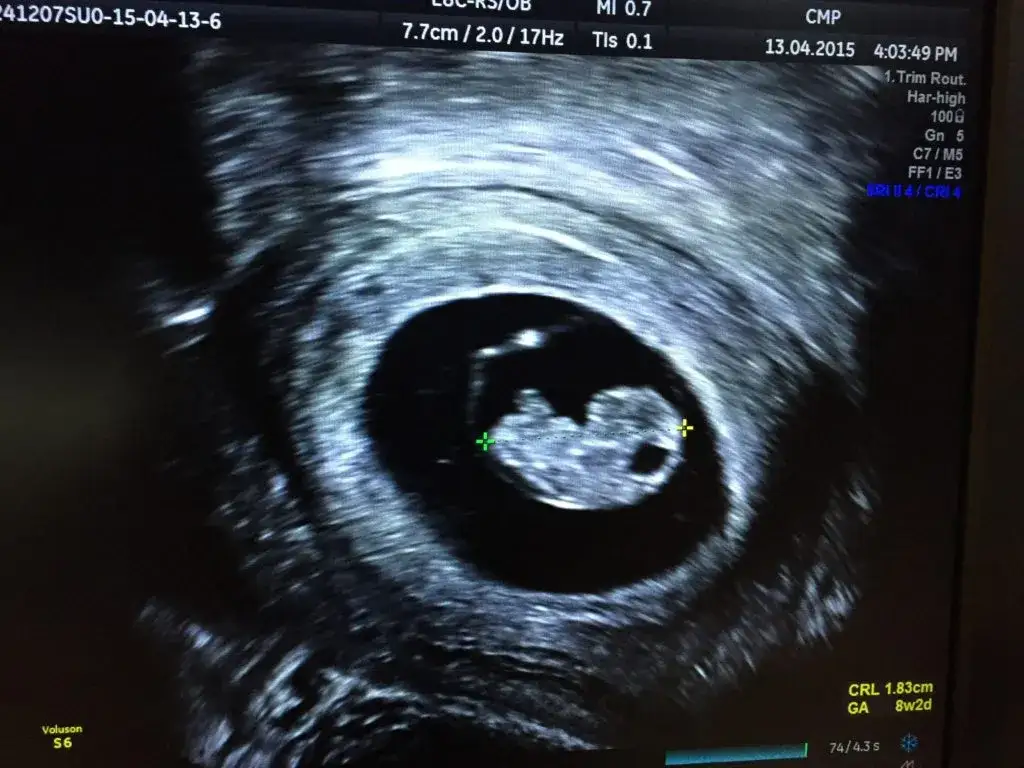

Dzięki wysokiej rozdzielczości nowoczesnych aparatów USG dopochwowe jest w stanie uwidocznić ciążę bardzo wcześnie. Z mojego doświadczenia wiem, że już około 5. tygodnia ciąży (licząc od pierwszego dnia ostatniej miesiączki) możliwe jest uwidocznienie w jamie macicy niewielkiego pęcherzyka ciążowego. Jest to pierwszy widoczny znak ciąży. Następnie, około 6. tygodnia, w pęcherzyku ciążowym pojawia się pęcherzyk żółtkowy, a tuż po nim, między 6. a 7. tygodniem, możemy już zobaczyć sam zarodek i, co najważniejsze, zarejestrować jego czynność serca. To właśnie obecność zarodka z bijącym sercem jest ostatecznym potwierdzeniem żywej ciąży wewnątrzmacicznej.

Co lekarz widzi na monitorze? Od pęcherzyka ciążowego do bicia serca

Obraz na monitorze USG we wczesnej ciąży to fascynująca podróż przez etapy rozwoju. Na początku, jak wspomniałam, widzimy czarny, okrągły pęcherzyk ciążowy, który jest wypełniony płynem i otoczony jasnym rąbkiem. To on świadczy o tym, że ciąża rozwija się w macicy. Następnie, wewnątrz pęcherzyka ciążowego, pojawia się mniejszy, okrągły pęcherzyk żółtkowy to on odżywia zarodek w pierwszych tygodniach. Kolejnym etapem jest uwidocznienie samego zarodka, który na początku jest zaledwie kilkumilimetrową strukturą. To moment, w którym często udaje się już zarejestrować delikatne, rytmiczne migotanie to właśnie bicie serca płodu. Widok bijącego serca jest zawsze niezwykle wzruszający i stanowi dla nas, lekarzy, potwierdzenie prawidłowego rozwoju ciąży.